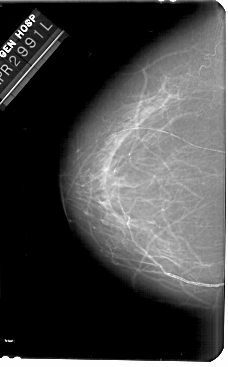

A_1681_1.RIGHT_CC

RIGHT_CC LINES 5401 PIXELS_PER_LINE 2941 BITS_PER_PIXEL 12 RESOLUTION 43.5 OVERLAY